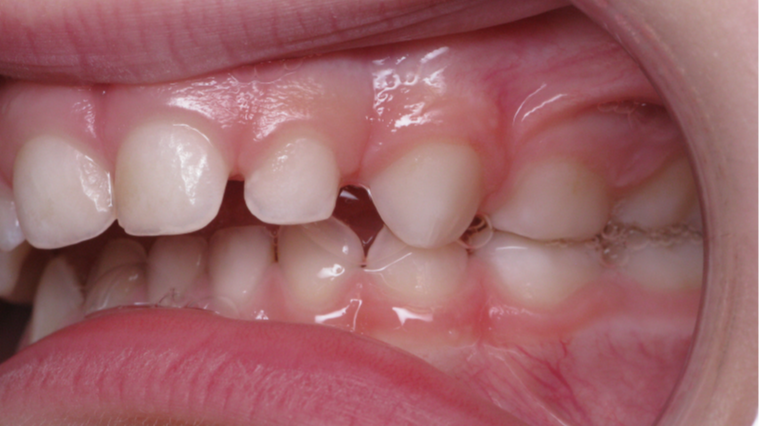

Décalage entre les dents d avant en arrière

appareillage mobile